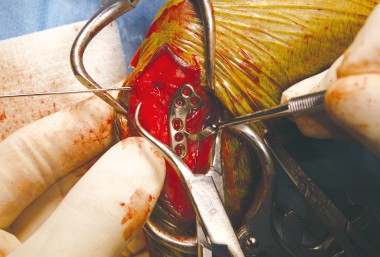

「もっと小さく、もっと精密に、もっと確実に固定できるプレートを」スワのTPLO開発は、臨床現場の切実な声から始まりました。小型犬や猫の細く繊細な脛骨に対応するには、従来製品とは一線を画す極小サイズでの高精度な加工が求められました。設計段階では、骨の形状に沿った最適な角度とカーブを導き出すため、専門医との密な連携のもと幾度もプロトタイプを見直し。

-

さらに、術中の取り回しやプレートの角度、穴の位置、術後の安定性に至るまで、現場の意見を反映しながら改良を重ねました。並行して、高水準の耐久試験と多数の臨床症例による検証を実施。

特に小型犬・猫では、インプラントがもたらす影響も大きいため、最小限のサイズで最大限の強度を実現する設計を徹底的に追求しました。 -

小型のTPLOプレートは、極小サイズでありながら高い耐久性と骨との適合性を両立する加工技術が求められました。独自の加工工程を構築し、強度試験・疲労耐久試験を繰り返し開発した製品です。しかし、製品の安全性は、臨床の現場での確認が必要であり専門医による100症例を超える臨床試験を繰り返し、術式、術後の経過を観察することにより製品の安全性を確認を進めています。

3穴タイプのスタンダード仕様ですが、臨床の中で小型の動物では最小骨量でも解剖学的に設置可能な2穴タイプが考案され、選択肢が広げられました。この製品は、臨床現場と開発製造の連携により開発されたTPLOプレートです。製品を届けて終わりとは考えていません。